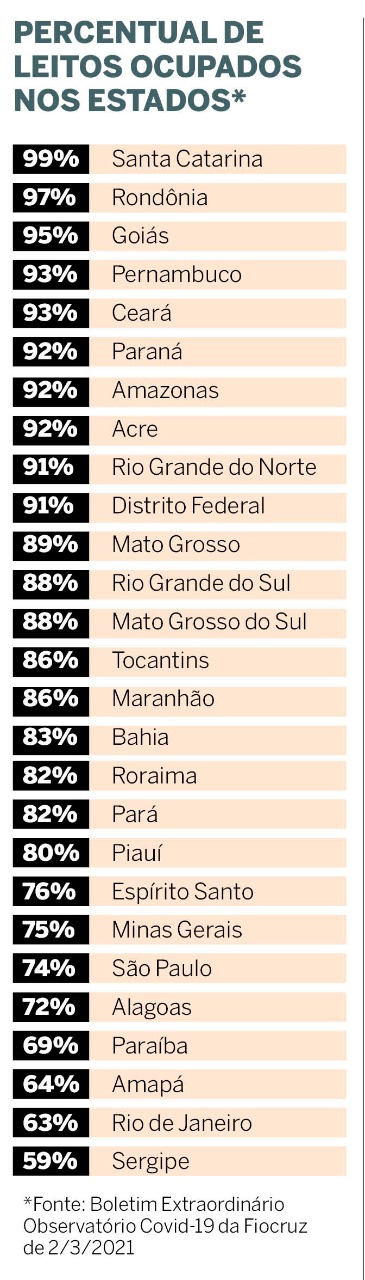

O Brasil perdeu 1.910 vidas na quarta-feira (3). Significa 1,3 morte a cada minuto e traduz um país acuado diante de uma escalada sombria. Dos dez maiores totais de mortes registradas em 24 horas desde o começo da pandemia, sete aconteceram nos primeiros meses de 2021. Três desses recordes ocorreram nos últimos dez dias e obrigaram a Fiocruz a lançar um boletim extraordinário sobre a evolução da doença.

mortes registradas em 24 horas desde o começo da pandemia, sete aconteceram nos primeiros meses de 2021. Três desses recordes ocorreram nos últimos dez dias e obrigaram a Fiocruz a lançar um boletim extraordinário sobre a evolução da doença.

Na noite de terça-feira, 2, a Fiocruz lançou um documento sobre a evolução da doença. Os pesquisadores afirmam no boletim que “os dados apresentados, embora alarmantes, constituem apenas a ponta do iceberg de um patamar de intensa transmissão no país”.

Mas epidemiologistas avaliam que as medidas ainda não são suficientes. O próprio boletim da Fiocruz recomenda medidas mais duras, como restrição de todas as atividades não essenciais, além de ampla testagem da população, rastreamento e isolamento de casos, aceleração da vacinação, abertura de novos leitos, reconhecimento legal do estado de emergência sanitária e aprovação de um plano de recuperação econômica com retorno imediato do auxílio emergencial para os mais pobres.

Segundo a análise da Fiocruz, a pandemia no Brasil acontece de maneira simultânea em todo o território, com tendência de crescimento e com iminente colapso dos sistemas de saúde em várias cidades. Três variantes circulam simultaneamente no país: a do Amazonas, do Reino Unido e da África do Sul. A do Amazonas deu origem a uma nova linhagem do vírus, a P2, encontrada no Rio de Janeiro. Das 27 capitais do país, 19 estão com taxas de ocupação de leitos de UTI-covid acima dos 80%. As mais críticas são Porto Velho (100%), Florianópolis (98%), Curitiba e Goiânia (95%), Natal (94%), Rio Branco e Campo Grande (93%). O Rio está com 88% de ocupação dos leitos.

Até o próximo dia 10, a previsão é que o país ultrapasse os 11 milhões de casos. “Em relação às mortes, nossa estimativa é de que o número de óbitos total anunciado é cerca de 60% do total real”, lamenta o pesquisador. E os problemas não param por aí. Segundo Domingos Alves, a defasagem em relação ao número de óbitos chega a 20 dias. É como se, olhando os números, tivéssemos mirando o retrovisor de um carro em movimento. E em alta velocidade. “Atingiremos 300 mil óbitos até 6 de abril, com média móvel de 1.500 mortes diárias até 14 de abril. E o cenário pode piorar por conta das mortes por falta de atendimento”.

Os estudiosos são uníssonos em dizer que a origem do caos sanitário, social e econômico do Brasil está no negacionismo do governo federal em relação à pandemia. “O Brasil nunca seguiu as orientações da Organização Mundial da Saúde para a flexibilização social”, afirmou Domingos Alves. Os indicadores são: declínio do número de mortes por pelo menos três semanas e queda de pelo menos 50% da incidência em um período de três semanas após o pico da pandemia; estrutura hospitalar para suportar a demanda; testagem em massa e em segmentos específicos; rastreamento de infectados. “É urgente que os estados comecem a fazer um lockdown efetivo de 15 a 21 dias para conter o desastre sanitário.

“Esse cenário que nós vivemos no Brasil é uma tragédia anunciada por toda a comunidade científica”. A fala acertiva é do pesquisador Domingos Alves, da USP, que participou de debate “Como Está a Pandemia Hoje”, organizado pelo Fórum de Ciência e Cultura da UFRJ, na segunda, 1º de março. Domingos integra a equipe de especialistas do Portal Covid-19 BR, ferramenta desenvolvida pela Universidade de São Paulo (USP) para acompanhamento e predição da pandemia no país. Há um ano, apenas quatro capitais eram responsáveis pelos casos de covid-19 no Brasil. Hoje, a pandemia se alastrou por todas as cidades. As festas clandestinas de final de ano e de carnaval contribuíram para tornar o quadro de alta transmissão predominante de norte a sul do país.

Para além das aglomerações em datas comemorativas, o isolamento social caiu a índices praticados antes do início da pandemia. Em todo o país, a taxa de isolamento média é de 31%, mesmo patamar de janeiro do ano passado. No Rio, o índice chega a 45%. Para o especialista, é preciso somar esforços com um lockdown efetivo e com aumento da cobertura vacinal. “O Brasil precisa aumentar em dez vezes a velocidade da vacinação para imunizar a população até o final do ano”, alerta Domingos Alves. “Aumento do número de leitos, isolar grupos de risco, isto é política de enxugar gelo, não está baseado na ciência”.

Expansão de leitos não é política de contenção da covid-19”.